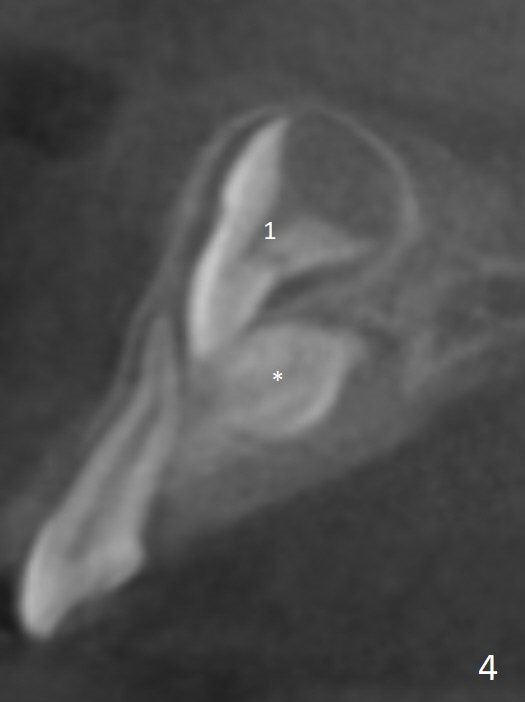

CBCT taken on 11/03/2017 confirms the findings mentioned above (Fig.2-4).  These 2 supernumerary teeth are close palatally (Fig.3 (for UR1), 4 (UL1)).